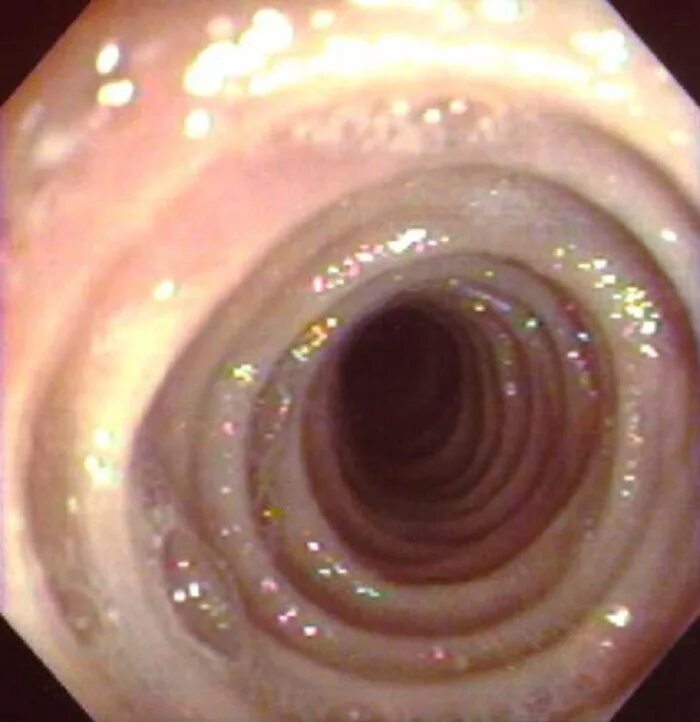

Кольцо шацкого в пищеводе что это